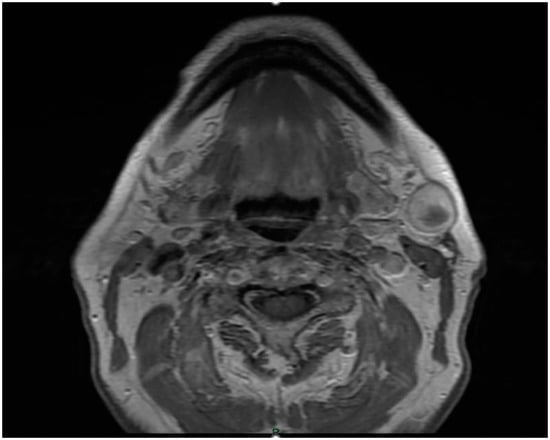

During the gathering of the medical history, the patient reported having undergone follow-up visits for the first five years but then missing subsequent appointments by personal choice. Physical examination revealed a well-circumscribed mass, mobile on both superficial and deep planes, not spontaneously painful or tender to palpation. For better characterization of the mass, an ultrasound-guided fine-needle aspiration biopsy was performed, which was reported as non-diagnostic. An MRI with contrast was then performed, which revealed “posteroinferiorly to the left submandibular gland, the presence of a nodulation approximately 2.3 × 1.6 cm, solid with a central internal area showing fluid signal with signal restriction in Diffusion Weighted Imaging (DWI) and heterogeneous enhancement with contrast media” [Figure 1]. No suspicious lymph nodes indicative of disease involvement were observed on this MRI scan. Additionally, a chest CT scan was performed, and no lesions suspicious for metastases were identified. Given these characteristics, the decision was made to proceed with surgical removal of the lesion without neck dissection, as there was no evidence of malignancy of the lesion. This approach was also deemed appropriate considering the patient’s comorbidities and the inability to discontinue anticoagulant therapy.

Figure 1. MRI image: a nodulation of approximately 2.3 × 1.6 cm is observed, solid with an internal central area showing fluid signal.